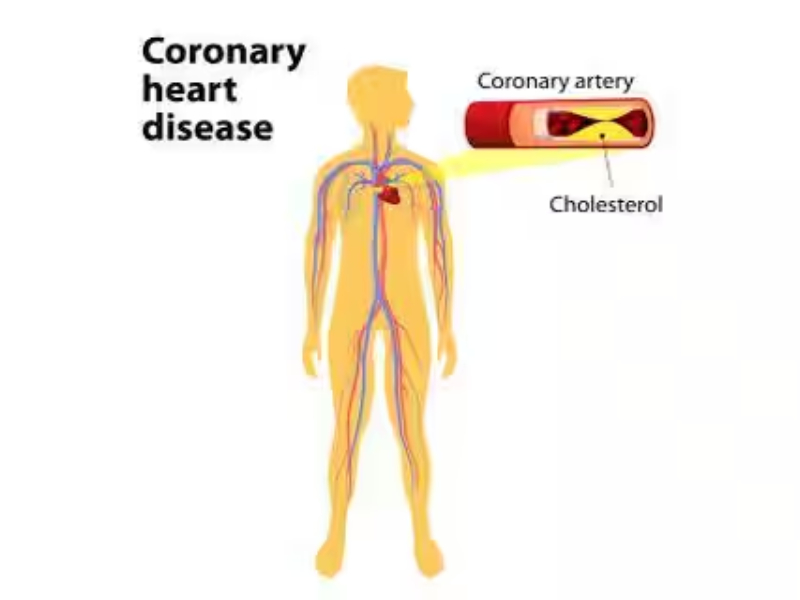

Heart disease is a broad term used to refer to a range of conditions that affect your heart. It includes blood vessel diseases like coronary artery disease, heart rhythm problems or arrhythmias, congenital heart defects and dilated cardiomyopathy among ot